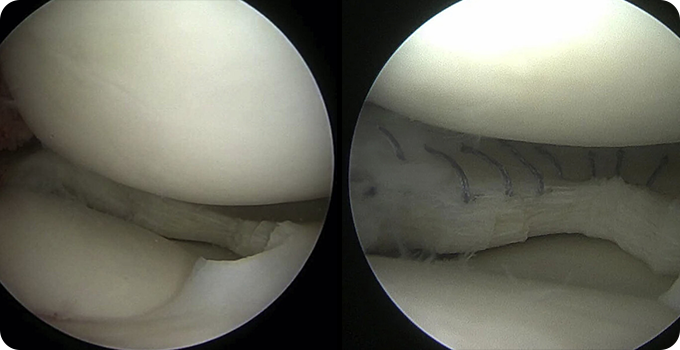

연골 봉합술&절제술 치료 사진

연골 봉합술&절제술

손상된 십자인대를 제거하고 새로운 인대를 이식하여 무릎 관절의 안정성을 회복하는 수술입니다. 이 수술은 관절내시경을 통해 진행되며, 최소 절개로 합병증 위험을 줄이고 회복 속도를 높이는 장점이 있습니다. 수술 후에는 체계적인 재활 프로그램을 통해 관절 가동 범위를 회복하고 근력을 강화하며, 일상생활로의 복귀를 목표로 합니다.

• 내시경적

치료

• 5mm 이하의

최소절개

• 안전한

치료방법

• 빠른

일상생활 복귀